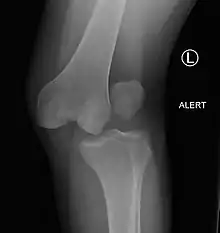

A lateral dislocation of the knee

They may be divided into five types: anterior, posterior, lateral, medial, and rotatory.[4] This classification is based on the movement of the tibia with respect to the femur.[11] Anterior dislocations, followed by posterior, are the most common.[2] They may also be classified on the basis of which ligaments are injured.[2]